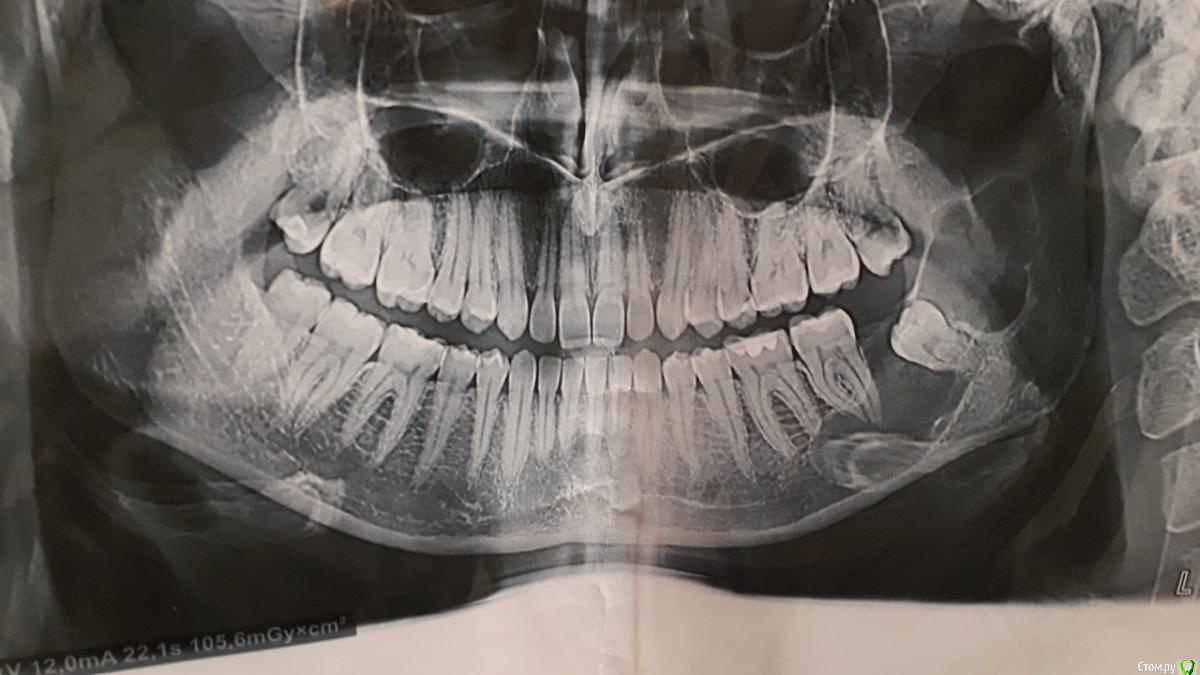

Екатерина 2235 Опубликовано 7 февраля, 2019 Поделиться Опубликовано 7 февраля, 2019 Здравствуйте,прошу совета.Недавно сделали снимок в клинике,по снимку сказали что у меня киста и зуб мудрости внутри и нужна операция.Подскажите,это не может быть ошибкой насчет кисты?И часто ли такое встречается в практике? Ссылка на комментарий

___49___ Опубликовано 7 февраля, 2019 Поделиться Опубликовано 7 февраля, 2019 (изменено) Здравствуйте,прошу совета.Недавно сделали снимок в клинике,по снимку сказали что у меня киста и зуб мудрости внутри и нужна операция.Подскажите,это не может быть ошибкой насчет кисты?И часто ли такое встречается в практике?Здравствуйте .Похоже , что ошибки нет (точный диагноз будет только после гистологического заключения) . Производить хирургическое вмешательство необходимо, откладывать в долгий ящик не советую . В каком учреждении будите производить операцию ? Изменено 7 февраля, 2019 пользователем ___49___ Ссылка на комментарий

Екатерина 2235 Опубликовано 8 февраля, 2019 Автор Поделиться Опубликовано 8 февраля, 2019 сделайте кт, загрузите сюдая загрузила,в самом начале Ссылка на комментарий

Гарриевич Опубликовано 8 февраля, 2019 Поделиться Опубликовано 8 февраля, 2019 это не Компьютерная Томограмма, а вам желательно сделать именно ее Ссылка на комментарий